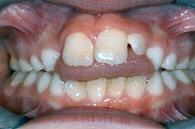

| Kreuzbiss seitlich | Zahnengstand | |